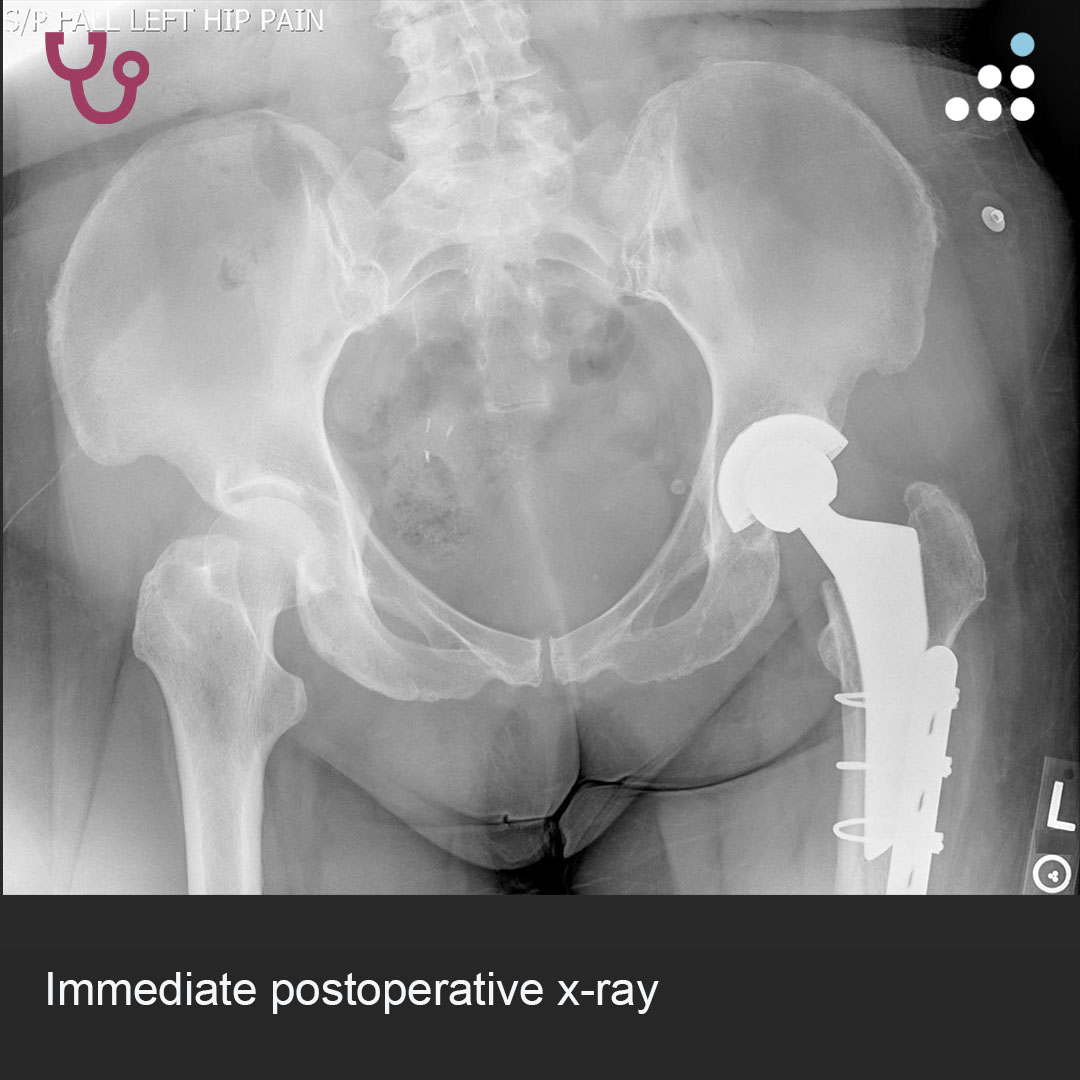

Can you answer our free question of the day? A patient presents to the trauma bay after involvement in a motor vehicle collision. Radiographs obtained in the trauma bay demonstrate a right distal femur fracture, as seen in Figure A. In surgery, the articular block is reduced, and reduction is held with headless compression screws. A retrograde intramedullary nail is then placed. After nail advancement, a varus and recurvatum deformity is noted at the fracture site with intraoperative fluoroscopy, as demonstrated via illustrations in Figures B and C. Placement of blocking screws in which locations (A - H) from Figure B and C would help correct this deformity? 1. B + E 2. A + G 3. B + F 4. C + H 5. D + H QID: 217509 Comment your answer below, then check to see if you got it correct by clicking the link below to see the answer & explanation. bit.ly/3OxP8sP #orthopedics #orthopedicsurgeon #orthopaedics #orthopaedic #orthopedic #ortholife #orthobullets #orthoresidents #orthoresident #orthoresidency #medicalschool #medicalstudent #medstudent #doctor